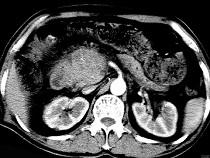

问题 男50岁黄疸进行性加重、腹部胀痛不适、食欲减退、体重减轻、上腹部可触及肿块,CT如图,最可能的诊断为 ( )

选项 A.急性胰腺炎 B.慢性胰腺炎 C.胰头癌 D.腹膜后淋巴瘤 E.转移瘤

答案 C